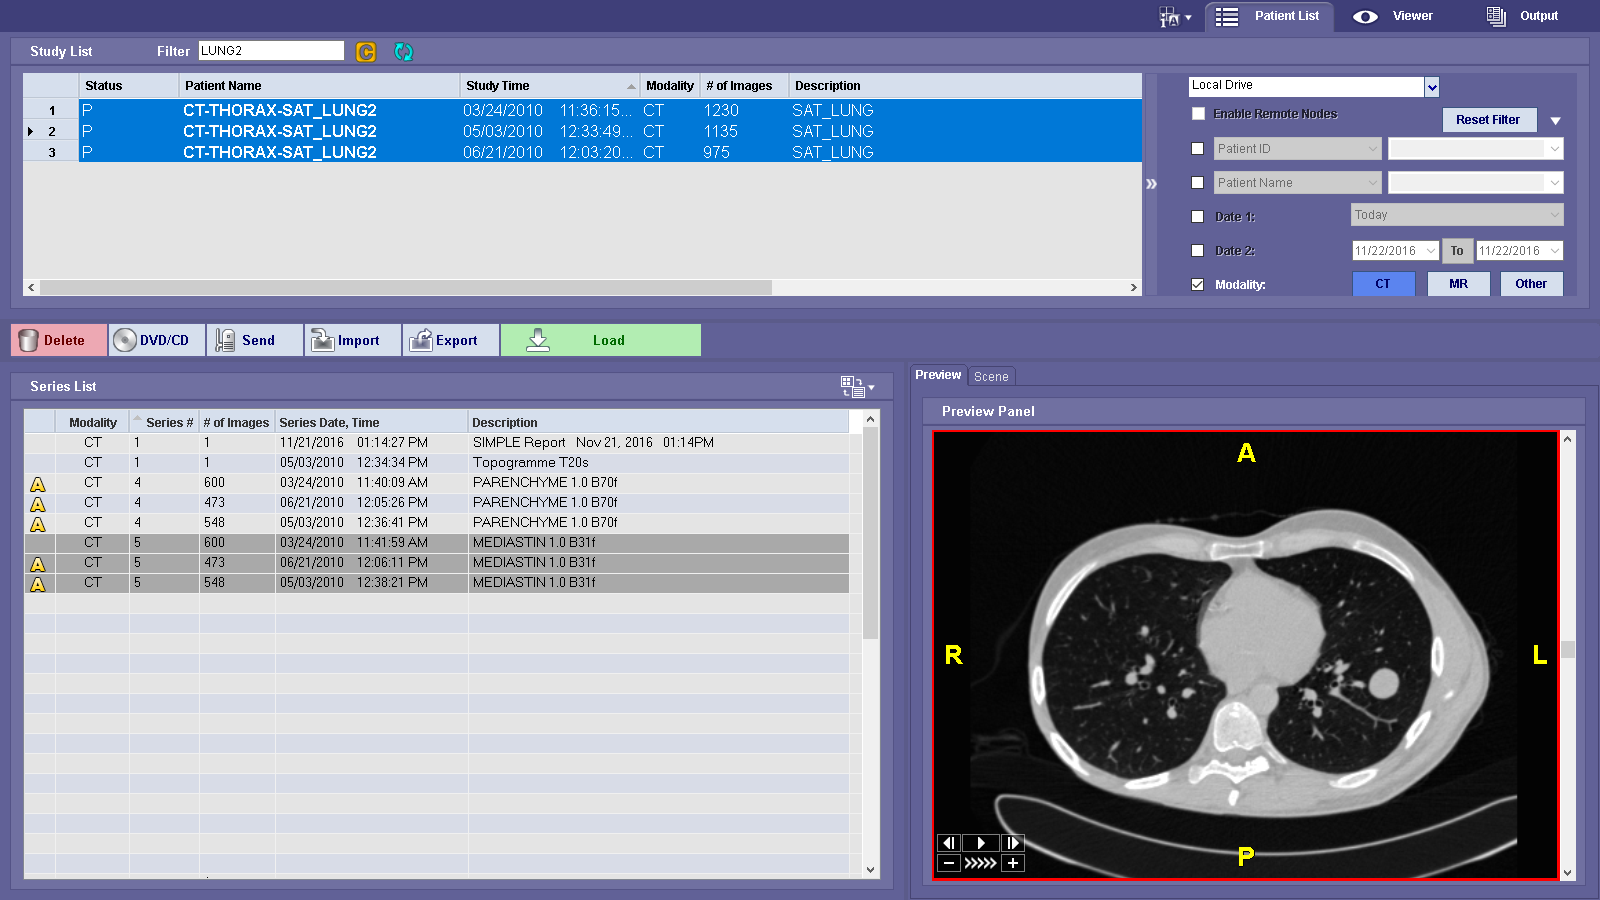

MT Lung workflow is a comprehensive lung analysis tool used to segment, analyze and track lung lesions over the course of time. SphereFinder allows a second look as the software helps identify spherical areas of interest. The Findings Viewer aids in tracking, classifying and measuring confirmed areas of interest. The Measurement Tracking feature tracks confirmed measurements over time.

MT Lung workflow is a comprehensive lung analysis tool used to segment, analyze and track lung lesions over the course of time. SphereFinder allows a second look as the software helps identify spherical areas of interest. The Findings Viewer aids in tracking, classifying and measuring confirmed areas of interest. The Measurement Tracking feature tracks confirmed measurements over time.

Gli studi comparativi verranno registrati automaticamente e sincronizzati al caricamento.